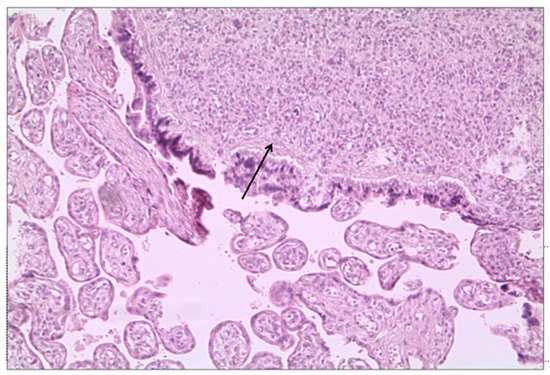

The features of fetal vascular malperfusion (FVM) were present in 25 cases (54%), including delayed villous maturation (n = 14 (30%)) (Figure 2), chorangiosis (n = 3 (6.5%)), villous edema (n = 13 (28%)), and mural fibrin deposition in fetal vessels (n = 1 (2%)) (Figure 2c).

Figure 2.

Signs of FVM in placenta from woman with SARS-CoV-2 infection. (a) Delayed villous maturation: increased number of large distal villi, with increased capillaries (↓), stromal macrophages (⇓), and diffused stromal oedema (hematoxylin-and-eosin stain; original magnification 10×). (b) Third trimester placenta with fibrosis of the villi and mural fibrin deposition (hematoxylin-and-eosin stain; original magnification 10×).